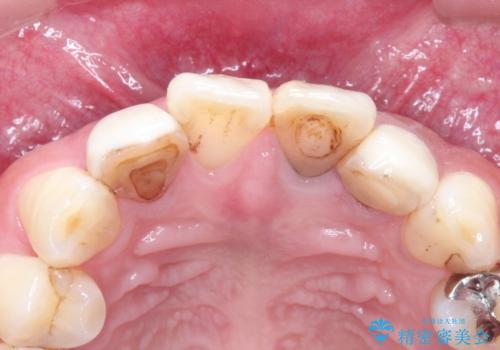

- 全体的なガタガタと前歯をきれいにしたいとのことで来院されました。

下の歯は重度のガタガタがあり、上の前歯は何本かが神経の治療がしてある状態でした。

インビザラインにて歯並びを整え、上顎の前歯にセラミックを装着する計画としました。

- 天然歯を削ります